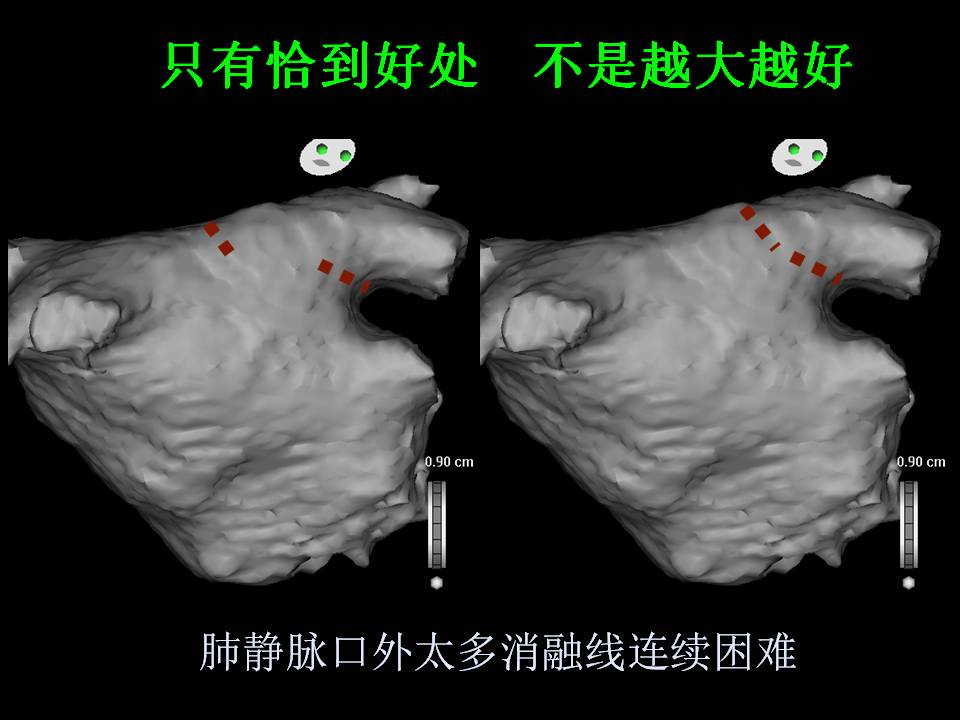

肺静脉隔离术难点

董建增